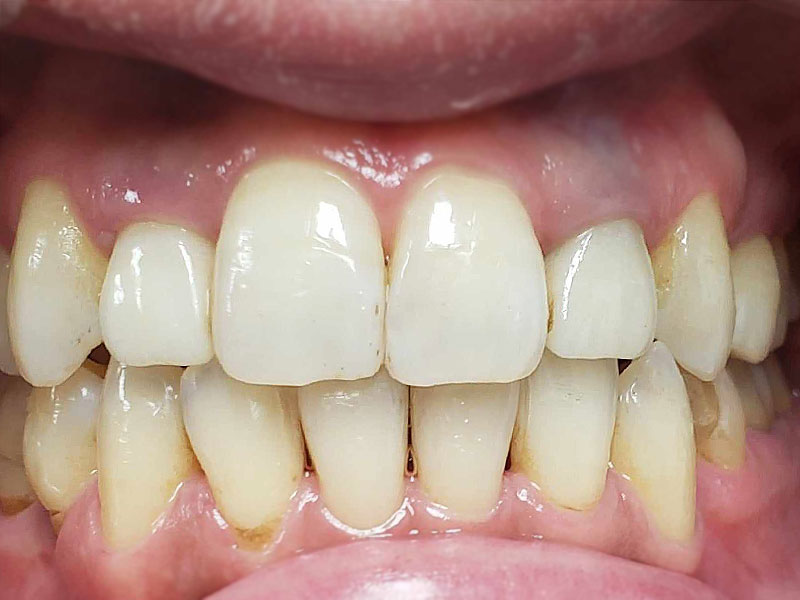

術後

約2年治療期間で包括矯正治療は完結となり、患者さんは大変満足してくれました。更にかみしめ癖も軽減し、肩こりも無くなったとのことです。口腔内写真からも舌房が確保され、舌圧痕がなくなり、かみしめ癖が軽減したことも十分にわかります。

(注、矯正治療して歯並びを治したら、肩こり、不定愁訴がなくなるわけではないことは断言しておきます。かみしめ癖が無くなっただけです。)

術後10年後

着色は認められますが、ほぼ10年前の状態を維持しているように思えます。着色したCRをセラミックにという考え方もありますが、神経除去のリスクもあるため、患者さんが見た目でどおしてもと希望されないかぎり、個人的にはお勧めしません。この方も希望されませんでしたが、症状を訴えたり、確実に中が虫歯と判断しない限り、このまま経過観察していこうと考えています。